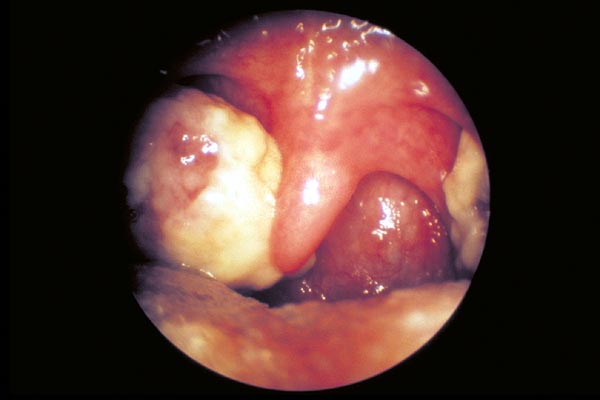

Pfeiffersches Drüsenfieber

|